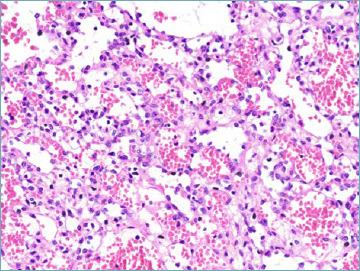

Mesenchymal tumours represent one of the most challenging field of diagnostic pathology and refinement of classification schemes plays a key role in improving the quality of pathologic diagnosis and, as a consequence, of therapeutic options. The recent publication of the new WHO classification of Soft Tissue Tumours and Bone represents a major step toward improved standardization of diagnosis. Importantly, the 2020 WHO classification has been opened to expert clinicians that have further contributed to underline the key value of pathologic diagnosis as a rationale for proper treatment. Several relevant advances have been introduced. In the attempt to improve the prediction of clinical behaviour of solitary fibrous tumour, a risk assessment scheme has been implemented. NTRK-rearranged soft tissue tumours are now listed as an "emerging entity" also in consideration of the recent therapeutic developments in terms of NTRK inhibition. This decision has been source of a passionate debate regarding the definition of "tumour entity" as well as the consequences of a "pathology agnostic" approach to precision oncology. In consideration of their distinct clinicopathologic features, undifferentiated round cell sarcomas are now kept separate from Ewing sarcoma and subclassified, according to the underlying gene rearrangements, into three main subgroups (CIC, BCLR and not ETS fused sarcomas) Importantly, In order to avoid potential confusion, tumour entities such as gastrointestinal stroma tumours are addressed homogenously across the different WHO fascicles. Pathologic diagnosis represents the integration of morphologic, immunohistochemical and molecular characteristics and is a key element of clinical decision making. The WHO classification is as a key instrument to promote multidisciplinarity, stimulating pathologists, geneticists and clinicians to join efforts aimed to translate novel pathologic findings into more effective treatments.